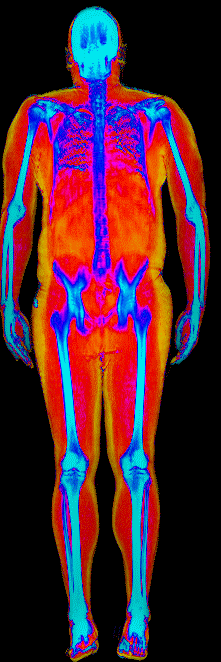

Each colorized scan shows the distribution of fat tissue (shown in warmer colors) and lean tissue (cooler colors) throughout the body. Compare your own DEXA scan to others in your range, or see what different body fat levels actually look like on a scan.

Male DEXA Scans by Body Fat %

10 to 15% body fat

15 to 20% body fat

20 to 25% body fat

25 to 30% body fat